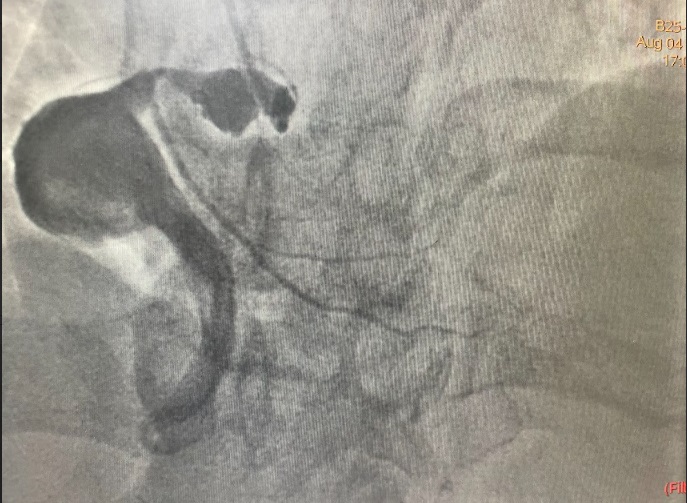

Coronary angiography showed a dominant RCA with a large proximal aneurysm measuring 4.5 ¡¿ 17 mm, with in-stent restenosis proximal to the aneurysm. Mid-to-distal RCA was ectatic. The LM, LAD, and LCx were also mildly ectatic but without significant stenoses. These findings were consistent with a giant RCA aneurysm, likely related to prior stent implantation.